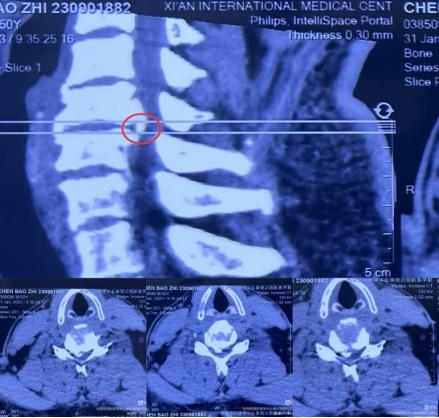

现年44岁的康先生(化名),出现了不明原因双手麻木、笨拙无力,并且症状逐渐在加重。经CT检查提示颈5-6椎间盘突出伴钙化,占位60%,严重压迫到周围的神经。

患者术前影像学资料: